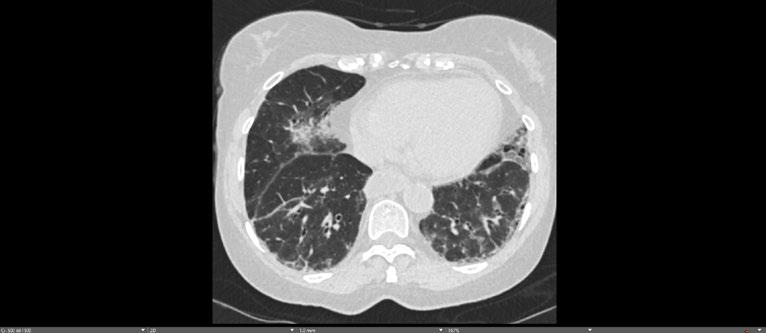

Radiogenomics Relationship of Nonsmall Cell Lung Cancer: Preliminary Results

Keywords: Cancer, lung, radiogenomics, radiology.

BACKGROUND AND AIMS

Radiomics, an emerging paradigm in medical imaging, entails the quantitative analysis of tumour features, and has exhibited potential in predicting treatment responses and outcomes. Furthermore, within the domain of -omics assessments, the significance of comprehensive genetic evaluation in non-small cell lung cancer (NSCLC) is on the rise, influenced by both biological and therapeutic considerations.

The aim of this study was to correlate radiomics features with the genetic results obtained from liquid biopsy in patients with lung tumours. The prediction of tumour genetics in radiomics relies on the presumption of conducting a non-invasive evaluation of molecular characteristics in tumour tissues, which can be challenging in certain tumour types, such as NSCLC. Therefore, in this context, the authors considered it pertinent to explore and generate hypotheses regarding the technical feasibility of identifying associations between genomics acquired through liquid biopsy assessments and radiomics.

MATERIALS AND METHODS

This observational, prospective study integrated radiomic perspectives using CT and genomic perspectives, through next-generation sequencing applied to liquid biopsies.

The authors included 62 patients with NSCLC who underwent pre-surgery CT (Revolution™ 128 MDCT, GE HealthCare, Chicago, Illinois, USA) at the Radiology Department of Campania University Luigi Vanvitelli, Naples, Italy. Every patient for whom liquid biopsy was performed gave informed consent for the genetic analysis. For the radiomic analysis, image processing CT volumes were manually delineated using ITK-SNAP 3.8.0 (University of Pennsylvania, Philadelphia, USA). Radiomics features (first order: Gray Level Co-occurrence Matrix, Gray Level Run Length Matrix, Gray Level Size Zone, Gray Level Dependence Matrix, and Neighbouring Gray Tone Difference Matrix) were computed using Pyradiomics1 in Python 3.7 (Python Software Foundation, USA) environment.

Radiomic features were derived from CT images, and genetic assessments were performed using a comprehensive panel targeting 523 cancerrelated genes. For the statistical analysis, association between radiomic features and gene mutations were assessed using feature importance based on receiver operating characteristic curve analysis; moreover, a machine learning approach based on support vector machine was used to evaluate the ability of radiomic features to predict gene mutations.

Associations between radiomic features and genetic mutations were established using the area under the receiver operating characteristic curve. Machine learning techniques, including support vector machine classification, aimed to predict genetic mutations based on radiomic features. The prognostic impact of selected gene variants was assessed using Kaplan–Meier curves and log-rank tests.

RESULTS

Sixty-two patients underwent screening, with 53 being comprehensively characterised radiomically and genomically. This group was predominantly male (68.4%), and adenocarcinoma was the prevalent histological type (73.7%). Most patients exhibited ECOG Performance Status of 0 or 1 (87.7%), and 91.2% had a history of former or current smoking. Disease staging was distributed across I–II (38.6%), III (31.6%), and IV (29.8%). Significant correlations were identified with mutations

Abstract ● ECR 2024 24 Radiology ● April 2024 ● Creative Commons Attribution-Non Commercial 4.0

of ROS1 p.Thr145Pro (shape_Sphericity), ROS1 p.Arg167Gln (glszm_ZoneEntropy, firstorder_TotalEnergy), ROS1 p.Asp2213Asn (glszm_GrayLevelVariance, firstorder_ RootMeanSquared), and ALK p.Asp1529Glu (glcm_Imc1). Patients with the ROS1 p.Thr145Pro variant demonstrated markedly shorter median survival compared to the wild-type group (9.7 months versus not reached; p=0.0143; hazard ratio: 5.35; 95% confidence interval: 1.39–20.48).

CONCLUSION

This study contributes to advancing the prediction of cancer genetics through the application of non-invasive radiomic techniques. The prediction of tumour genetics in radiomics hinges on the assumption of conducting a non-invasive assessment of molecular characteristics in tumour tissues, which can pose challenges in certain tumour types, such as NSCLC. Therefore, within this context, the authors deemed it relevant to explore and formulate hypotheses regarding the technical feasibility of identifying associations between genomics obtained through liquid biopsy assessments and radiomics.

Specific radiomic features illustrate the capability to predict non-synonymous mutations of ROS1 and ALK in patients with NSCLC. Investigating the prediction of cancer genetics using non-invasive radiomic techniques represents an innovative frontier in scientific research, which is currently undergoing extensive investigation. Research on the use of conventional CT features and CT image-based radiomic features to predict the gene mutation status of lung cancer is still in its nascent stages.

The integration of radiomic techniques in predicting cancer genetics holds potential, but is constrained by cost and technological limitations. Despite these challenges, the authors’ study explores the relationships between genomics and radiomics, revealing specific genetic variants associated with radiomic features. While acknowledging limitations, particularly the small sample size and the lack of actionable mutations, this research lays the groundwork for broader investigations aiming to link radiomics and genomics in NSCLC. The ultimate objective is to improve prognostic accuracy and refine therapeutic strategies. ●